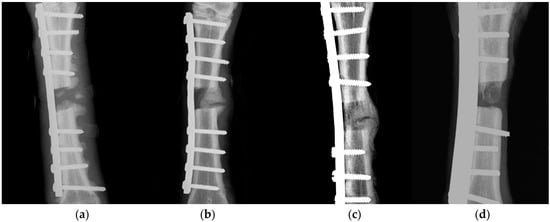

3.3.1. Radiographic Examination

- Corrales, L.A.; Morshed, S.; Bhandari, M.; Miclau, T. Variability in the assessment of fracture-healing in orthopaedic trauma studies. J. Bone Jt. Surg. Am. 2008, 90, 1862–1868. [Google Scholar] [CrossRef] [PubMed]